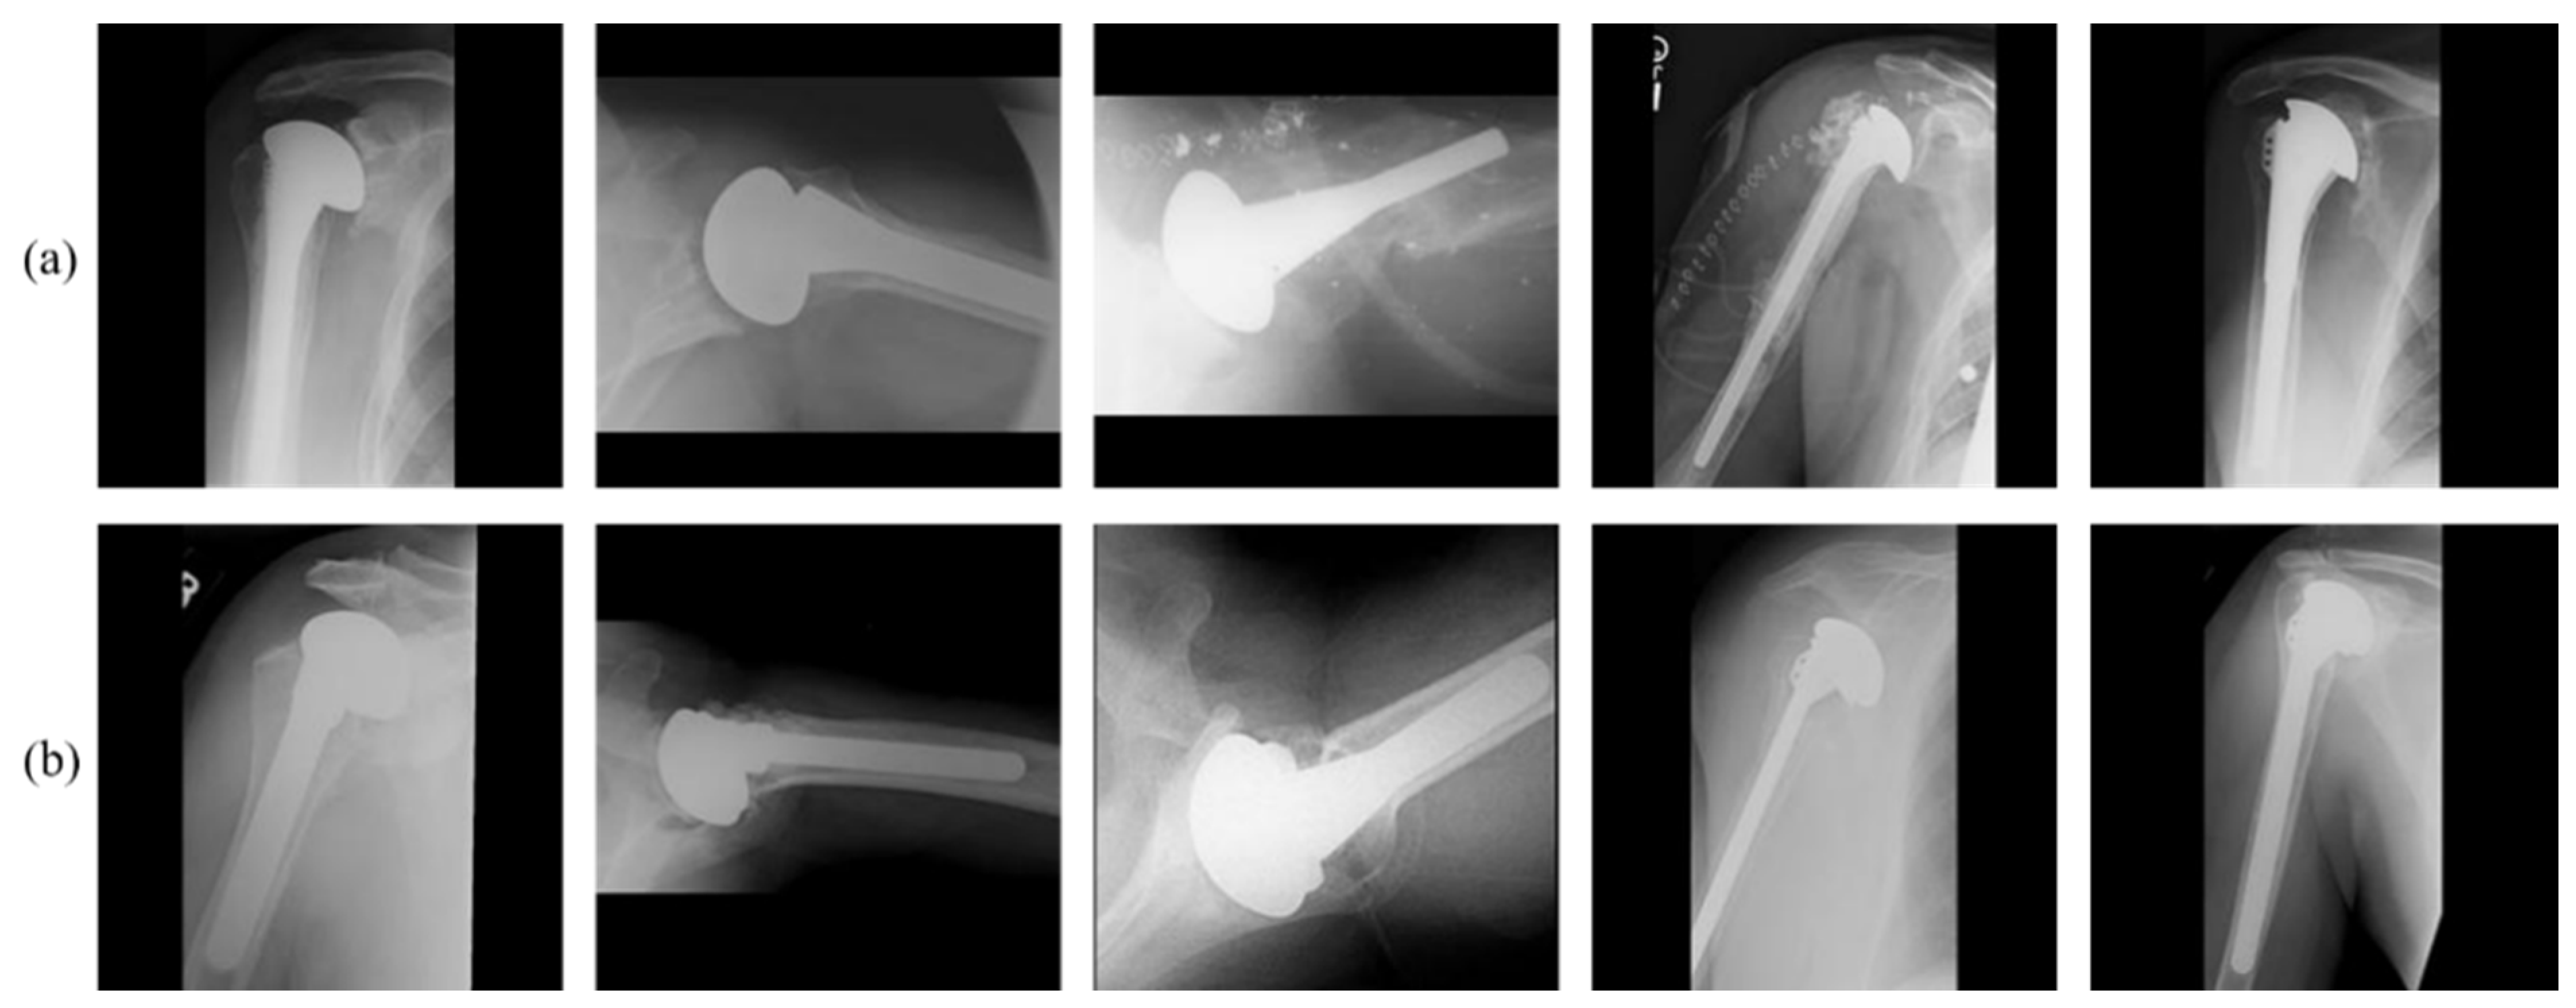

3.2. Rotational Invariant Augmentation (RIA)